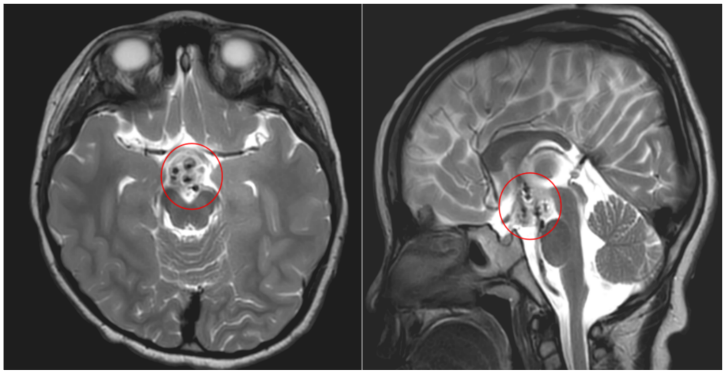

该院神经外八科二区(癫痫外科)副主任陈俊喜接诊后,与癫痫中心团队联合会诊,根据检查结果,诊断患儿为下丘脑错构瘤引发的痴笑样癫痫。“患儿的‘哭闹’表情,其实是痴笑样癫痫的表现。”陈俊喜介绍道。

在手术机器人辅助下,陈俊喜带领团队为患儿进行了立体定向脑电图(SEEG)微创置入手术,将6根电极精准置入患儿颅内瘤体,确定放电核心位点后进行微创热凝毁损治疗,解决患儿癫痫发作的情况。